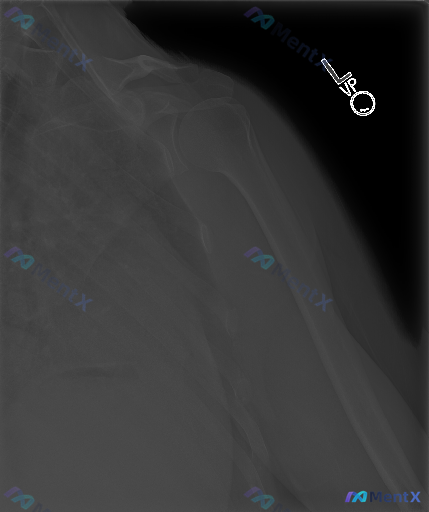

整理到一张左侧肱骨X光正位片的读片资料,影像科的客观描述如下: 1. 骨皮质连续性:肱骨干近、中、远端未见明确骨折线、皮质台阶感或成角畸形,连续性良好;骨小梁结构清晰,无压缩或不规则透亮区。 2. 关节对位:肩关节(肱骨头与肩胛盂)、肘关节(肱尺、肱桡关节)对位良好,关节间隙正常,无脱位/半脱位征象...